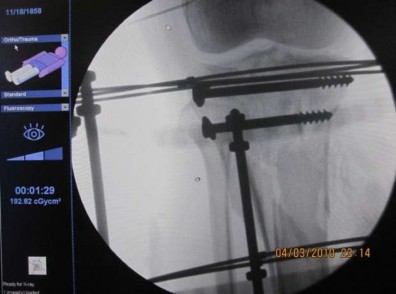

Hình 2.8. Máy C-arm kiểm tra kết quả nắn, quá trình kết hợp xương tối thiểu và kết quả cuối cuộc mổ

Hình 2.9. Màn hình máy C-arm cho thấy các mảnh gãy đã được nắn và cố định đạt yêu cầu